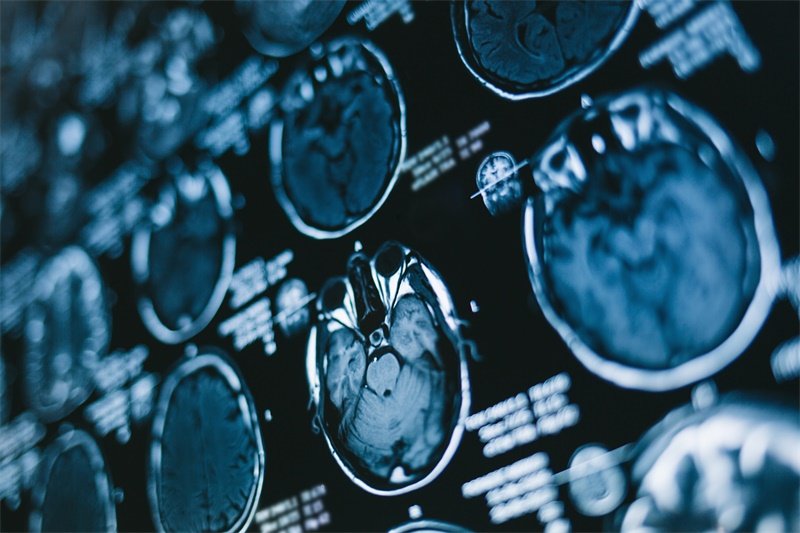

该肿瘤的识别靠的是临床症状、影像学检查以及组织学的确诊。骶骨脊索瘤比较少见,因此许多医务人员可能对此相对较生疏,导致治疗延误,因此早期关注症状至关重要。

骶骨脊索瘤的诊断通常依赖于影像学检查,例如X光、CT或MRI等,这些检查可以帮助医生观察肿瘤的大小、形状以及对周围组织的影响。此外,组织切片检验也是确诊骶骨脊索瘤的重要手段之一。其他血液检查和历史症状分析有助于更全面地了解患者病情。